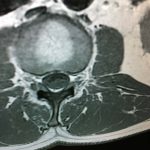

Εικόνα 5 α,β, Μαγνητική τομογραφία (Σεπτέμβριος 2017) μετωπιαίες λήψεις (coronal), γ,δ, εγκάρσιες λήψεις (axial) ,ε,στ,ζ,η οβελιαίες λήψεις (saggital). Παρατηρείται αύξηση των διαστάσεων ,του αιμαγγειώματος σε σύγκριση με εκείνες του 2002.